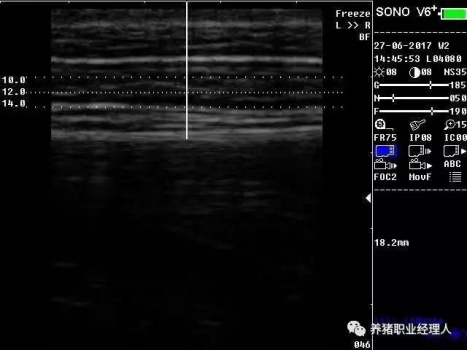

根據(jù)以上表格,活體測(cè)膘與實(shí)體測(cè)膘的相關(guān)分析及活體膘厚與胴體瘦肉率的相關(guān)分析結(jié)果證明,最后肋骨處和腰薦結(jié)合處離背中線(xiàn)5cm處(B5、C5)可作為活體測(cè)膘的最佳部位。 根據(jù)中華人民共和國(guó)農(nóng)業(yè)行業(yè)標(biāo)準(zhǔn)(NY/822-2004)種豬生產(chǎn)性能測(cè)定規(guī)程規(guī)定:生產(chǎn)性能背膘值運(yùn)用A超儀器測(cè)量的需測(cè)定腰薦椎結(jié)合處(P1)、胸腰椎結(jié)合處(P2)距背中線(xiàn)左側(cè)5cm處,兩點(diǎn)背膘厚平均值。生產(chǎn)性能背膘值運(yùn)用B超儀器測(cè)量的需測(cè)定倒數(shù)第三和第四肋骨間距背中線(xiàn)左側(cè)5cm處背膘厚。 2.3 剔剪剪毛 因?yàn)槌暡ㄊ遣荒茉诳諝庵袀鞑サ?,所以在利用儀器測(cè)量之前,先用剔剪剪去測(cè)定部位的豬毛,方便測(cè)量?jī)x器探頭與豬皮膚的無(wú)縫接觸。剪毛面積一般為5cm×5cm左右。此時(shí)若皮膚死皮結(jié)痂較多,便可用溫水擦洗去痂。 2.4涂耦合劑 耦合劑是檢測(cè)儀探頭與豬皮膚之間的中間潤(rùn)滑劑,作為超聲波從儀器發(fā)出到豬體表和從豬體表回到儀器的傳播介質(zhì)。所以耦合劑的作用是排除探頭與豬體表之間的空氣和作為超聲波傳播的介質(zhì)。它是準(zhǔn)確測(cè)定背膘所不能缺少的。 2.5 正確測(cè)量 因?yàn)樨i體表脂肪分為三層。所以不管是用A超還是B超,我們一般都能同時(shí)測(cè)量到三個(gè)數(shù)值,而正確反映豬只體況的是第三個(gè)數(shù)值。如圖所示:

測(cè)量時(shí),盡量讓豬只安靜,避免豬只弓背或塌腰而使測(cè)量數(shù)據(jù)出現(xiàn)偏差。探頭應(yīng)直線(xiàn)平面與豬背正中線(xiàn)縱軸面垂直,不可斜切。同時(shí)探頭應(yīng)與豬背密接且不重壓。 2.6 讀取記錄數(shù)據(jù) 若為A超,讀取儀器亮三個(gè)指示燈時(shí)的數(shù)值,記錄下來(lái)。若為B超,觀察并調(diào)節(jié)屏幕影響,獲得理想影像時(shí)即凍結(jié)影像,測(cè)量背膘厚和眼肌面積,并加以說(shuō)明標(biāo)記。影響打印或保存處理。 3、通過(guò)背膘測(cè)定指導(dǎo)豬生產(chǎn)飼喂管理 以妊娠母豬為例: 表3 妊娠母豬適宜背膘值范圍